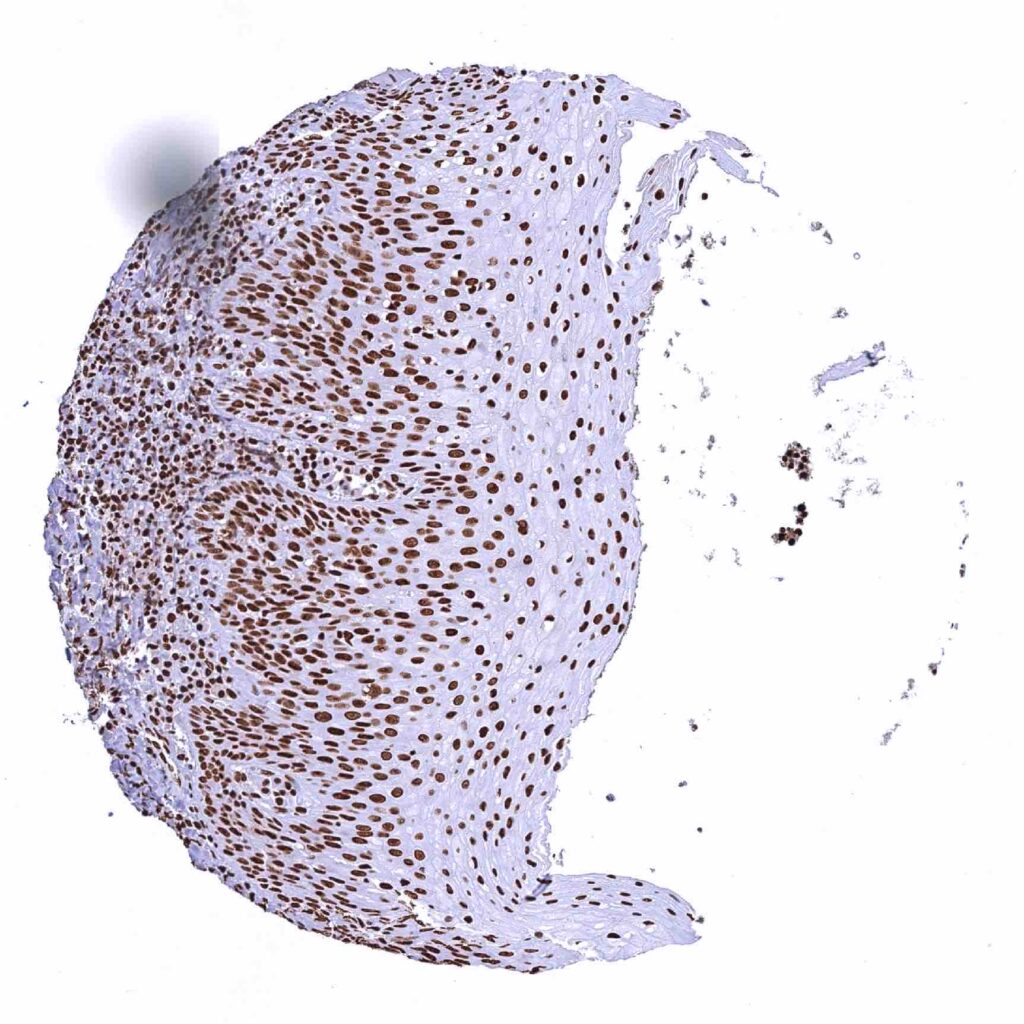

Esophagus, squamous epithelium – The intensity of nuclear TRIM28 staining decreases slightly from the basal to the top cell layers